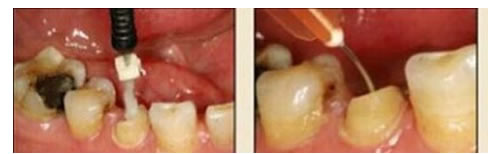

10.毛刷的選用

圖20:毛刷應用(錯誤) 圖21:根管專用毛刷

市場上毛刷的種類繁多,臨床應用比較雜亂。冠部牙體組織或各種修復體涂抹粘接劑時,由于粘接面視野清晰、范圍大,對毛刷的選擇一般無嚴格要求,臨床大多使用圓球形或鬃束狀毛刷;纖維樁修復時,由于根管樁道有深度且視野差,以上兩種毛刷很難伸入狹窄的樁道深部,無法保證粘接劑在整個樁道內(nèi)壁被均勻地涂抹(圖 20)。纖維樁粘接時應使用根管專用微型毛刷(圖 21),其形態(tài)和長度與樁道吻合,毛刷頭部可彎曲控制,可到達較深的根管底端,有利于粘接劑的均勻涂布。某些根管毛刷采用納米級刷毛,根管涂擦時可進入牙本質(zhì)小管和側(cè)枝根管,能較好地提高粘接效果。